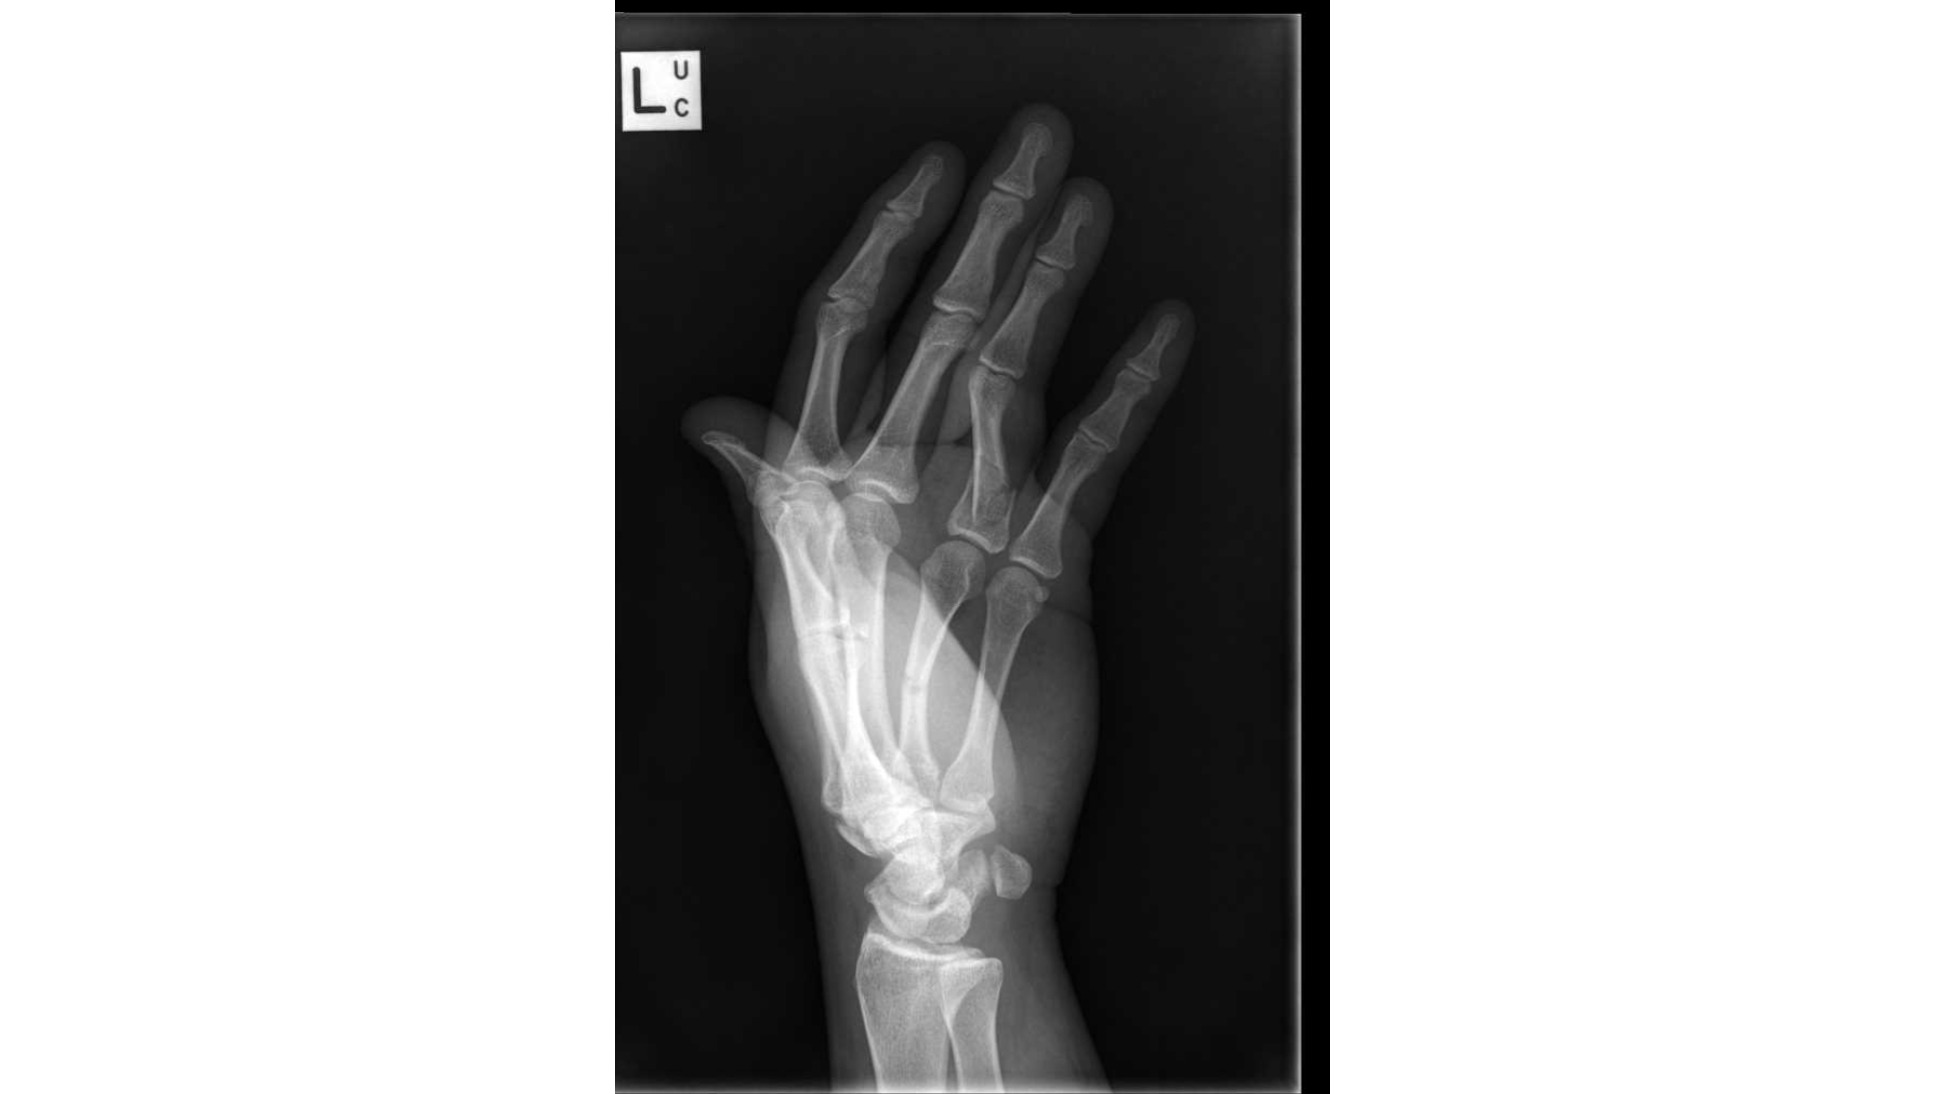

Raising funds for: Laurie Steel

On the 19th of September 2018 I crushed my left hand in a work place injury, I shattered my left ring finger into 14 pieces and dislocated the finger as well as snapping my metacarpal in half. I had surgery placing plates and screws in my hand, 3 weeks after my surgery i developed Complex Regional Pain Syndrome CRPS a debilitating pain condition that is the highest known pain level on the McGill Pain Scale. In the months after surgery and years now I still have CRPS and will most likely have it for life. I need to have my ring finger amputated due to it not bending at all after surgery, be that due to the plate or the crps itself it is something that has been spoken about with orthopaedic surgeons, the cost for my original surgery was over $46000 in 2018 so I would expect an amputation and removal of plates surgery to be atleast that much, unfortunately I have to cover that surgery out of my own pocket, and after paying lawyer fees and having centrelink claim some of the compensation money I received I had enough money to purchase a property in the hopes I could afford to move there to not have the cost of living expense such as rent power etc, I am suffering depression because of my situation and keep on having bad luck with vehicles and just everything in general, I am 25 and want to be able to support my wife and someday have a family, if my hand is corrected I may have a chance of working through the pain and rebuilding my left arms muscle mass after its depletion from lack of use due to the finger not bending and having crps pain that has spread from my hand all up my arm and into my shoulder. My shoulder drops out of joint all the time as result of this and I'm hoping I can repair it without surgery if it isn't already too late. I don't have high hopes of this working or of much of anything going my way and maybe that's just because of being depressed or maybe that's from having such bad luck since injuring my hand, I also cannot claim any kind of centrelink benefit until July 2023 so I have no income at all, only the one wage from my wife supporting us. I have attached photos of original injury, xray picture and a photo of my hand showing the ring finger the way it is when making a fist.